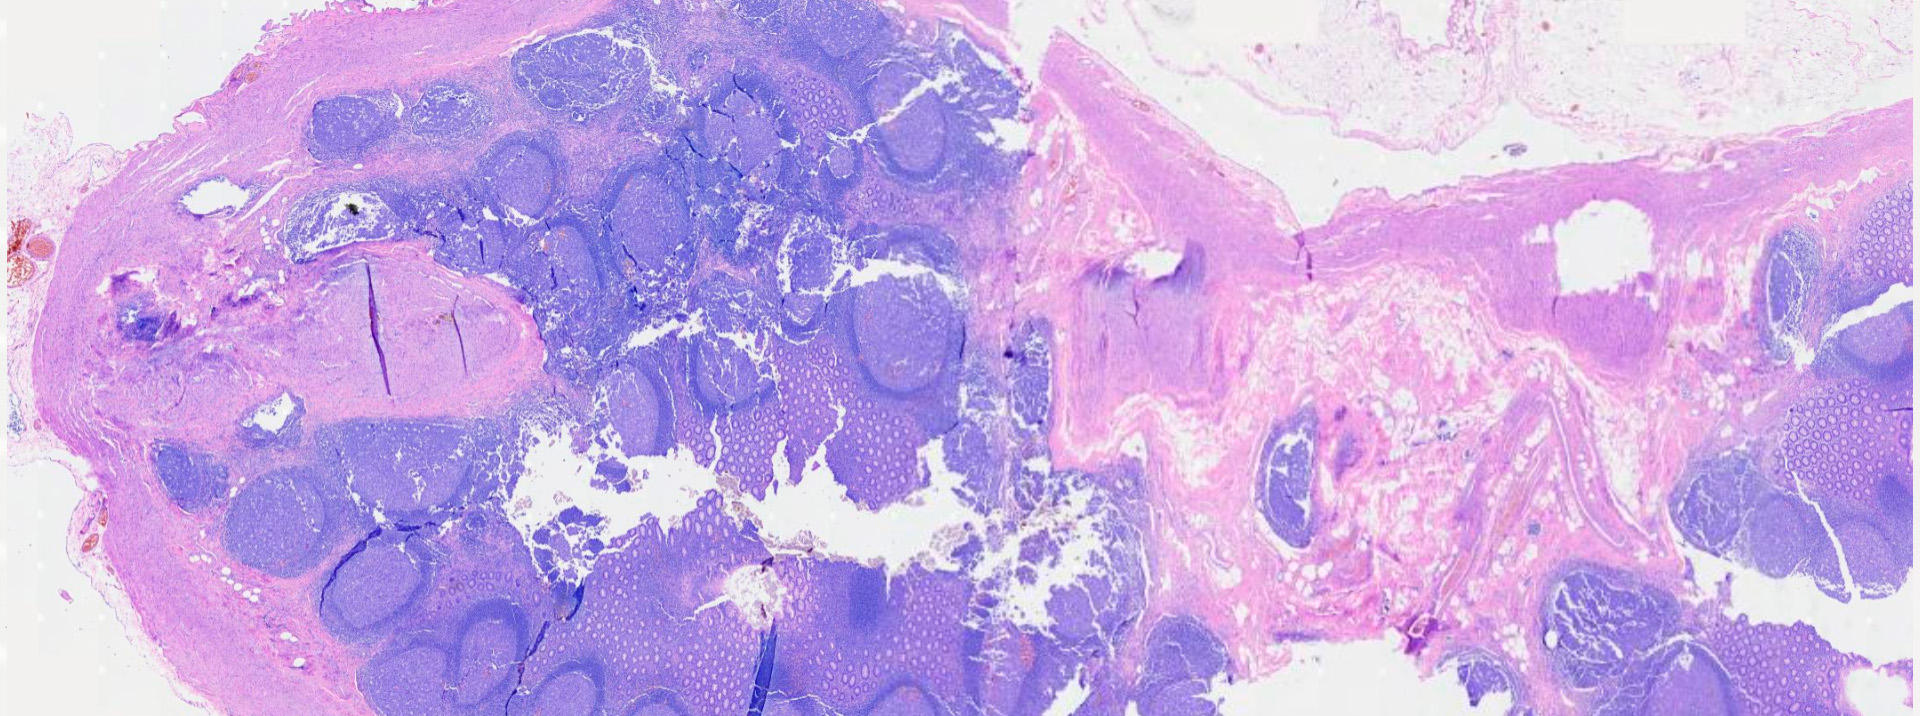

IMAGEN ESCANEADA

Trichinella spiralis en músculo

https://pathpresenter.net/public/display?token=24bac4c6

Trichinella spiralis (y otras especies)

CARACTERÍSTICAS: Nematodo tisular cuyo ciclo de vida se completa en un único hospedero, que actúa secuencialmente como hospedero definitivo (albergando adultos en el intestino) e intermediario (albergando larvas en el músculo).

• Larva Muscular (L1): Es la forma infectante y la etapa de resistencia. Mide aprox. 1.2 mm. Las larvas L1 liberadas por la hembra migran vía sanguínea o linfática hasta la musculatura estriada, donde penetran las fibras musculares. Allí, inducen la formación de una estructura de resistencia única llamada “célula nodriza”, dentro de la cual la larva se enrolla en espiral. Estas larvas encapsuladas pueden permanecer viables durante años.

UBICACIÓN: Adultos en el intestino delgado. Larvas (L1) enquistadas en el músculo esquelético (diafragma, maseteros, deltoides).

ESTADO INFECTANTE: Larva muscular (L1) enquistada en la “célula nodriza”, adquirida por consumo de carne cruda o mal cocida.